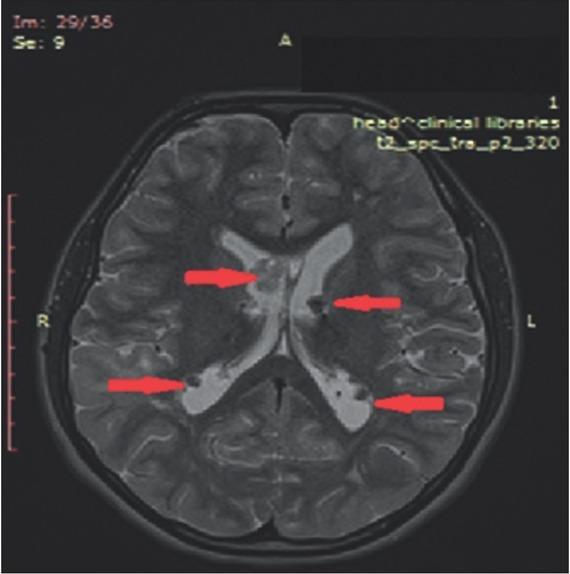

Tuberous sclerosis complex (TSC) is an autosomal-dominant multi system disorder. The genetic basis of the disorder is mutations in the or gene, which leads to over activation of the mammalian target of rapamycin (mTOR) protein complex and results in development of benign tumors in different body systems such as brain, skin, lungs and kidney. The mTOR inhibitors are presently the main treatment option for patients with TSC. We here report a 21-year female patient with large bilateral angiomyolipoma (AML) in both kidneys with longest diameter more than 12.3 cm and subependymal giant cell astrocytoma (SEGA). Treatment with everolimus (EVE) was initiated at a dose of 10.0 mg/day and continued during the following 3 years. Magnetic resonance imaging (MRI) was performed before treatment with everolimus was initiated, and consequently at 12 and 36 months for follow-up of the efficacy of the treatment. After 3 years, the total size of largest AML decreased by ~24.0% in the longest diameter. A reduction of the total size of SEGA was also observed. The most common adverse effect of treatment was stomatitis grades 3 to 4 and one febrile episode associated with skin rash that required a reduced dose of EVE. In conclusion, the everolimus treatment improved even such a large renal AML and the effect persisted during the long-term administration with a small number of adverse effects. A positive effect was observed on the brain tumor as well.

结节性硬化症(TSC)是一种常染色体显性遗传的多系统疾病。该疾病的遗传基础是 或 基因发生突变,这会导致雷帕霉素哺乳动物靶点(mTOR)蛋白复合物过度激活,进而在脑、皮肤、肺和肾等不同身体系统中引发良性肿瘤。mTOR 抑制剂目前是 TSC 患者的主要治疗选择。我们在此报告一名 21 岁女性患者,双侧肾脏患有直径超过 12.3 cm 的巨大血管平滑肌脂肪瘤(AML)以及室管膜下巨细胞星形细胞瘤(SEGA)。以 10.0 mg/天的剂量开始使用依维莫司(EVE)治疗,并在接下来的 3 年中持续使用。在开始使用依维莫司治疗前进行了磁共振成像(MRI)检查,并在治疗 12 个月和 36 个月时进行了随访,以评估治疗效果。3 年后,最大 AML 的最长直径总大小减少了约 24.0%。SEGA 的总大小也有所减小。治疗最常见的不良反应是 3 至 4 级口腔炎以及一次与皮疹相关的发热发作,这需要减少依维莫司的剂量。总之,依维莫司治疗改善了如此大的肾 AML,且在长期给药期间效果持续,不良反应较少。对脑肿瘤也观察到了积极效果。